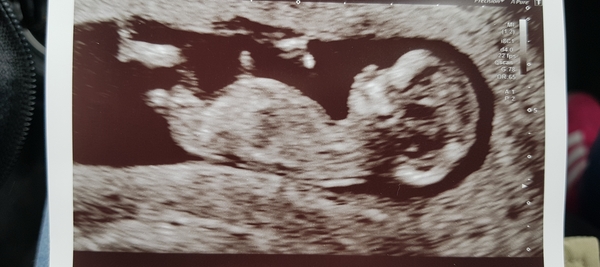

12 week scan went well Smile they've moved me forward by 4 days so now due on 12th September, yipee! Such a relief to have this first scan over and done with.

Lovely scan baby. Congratulations!